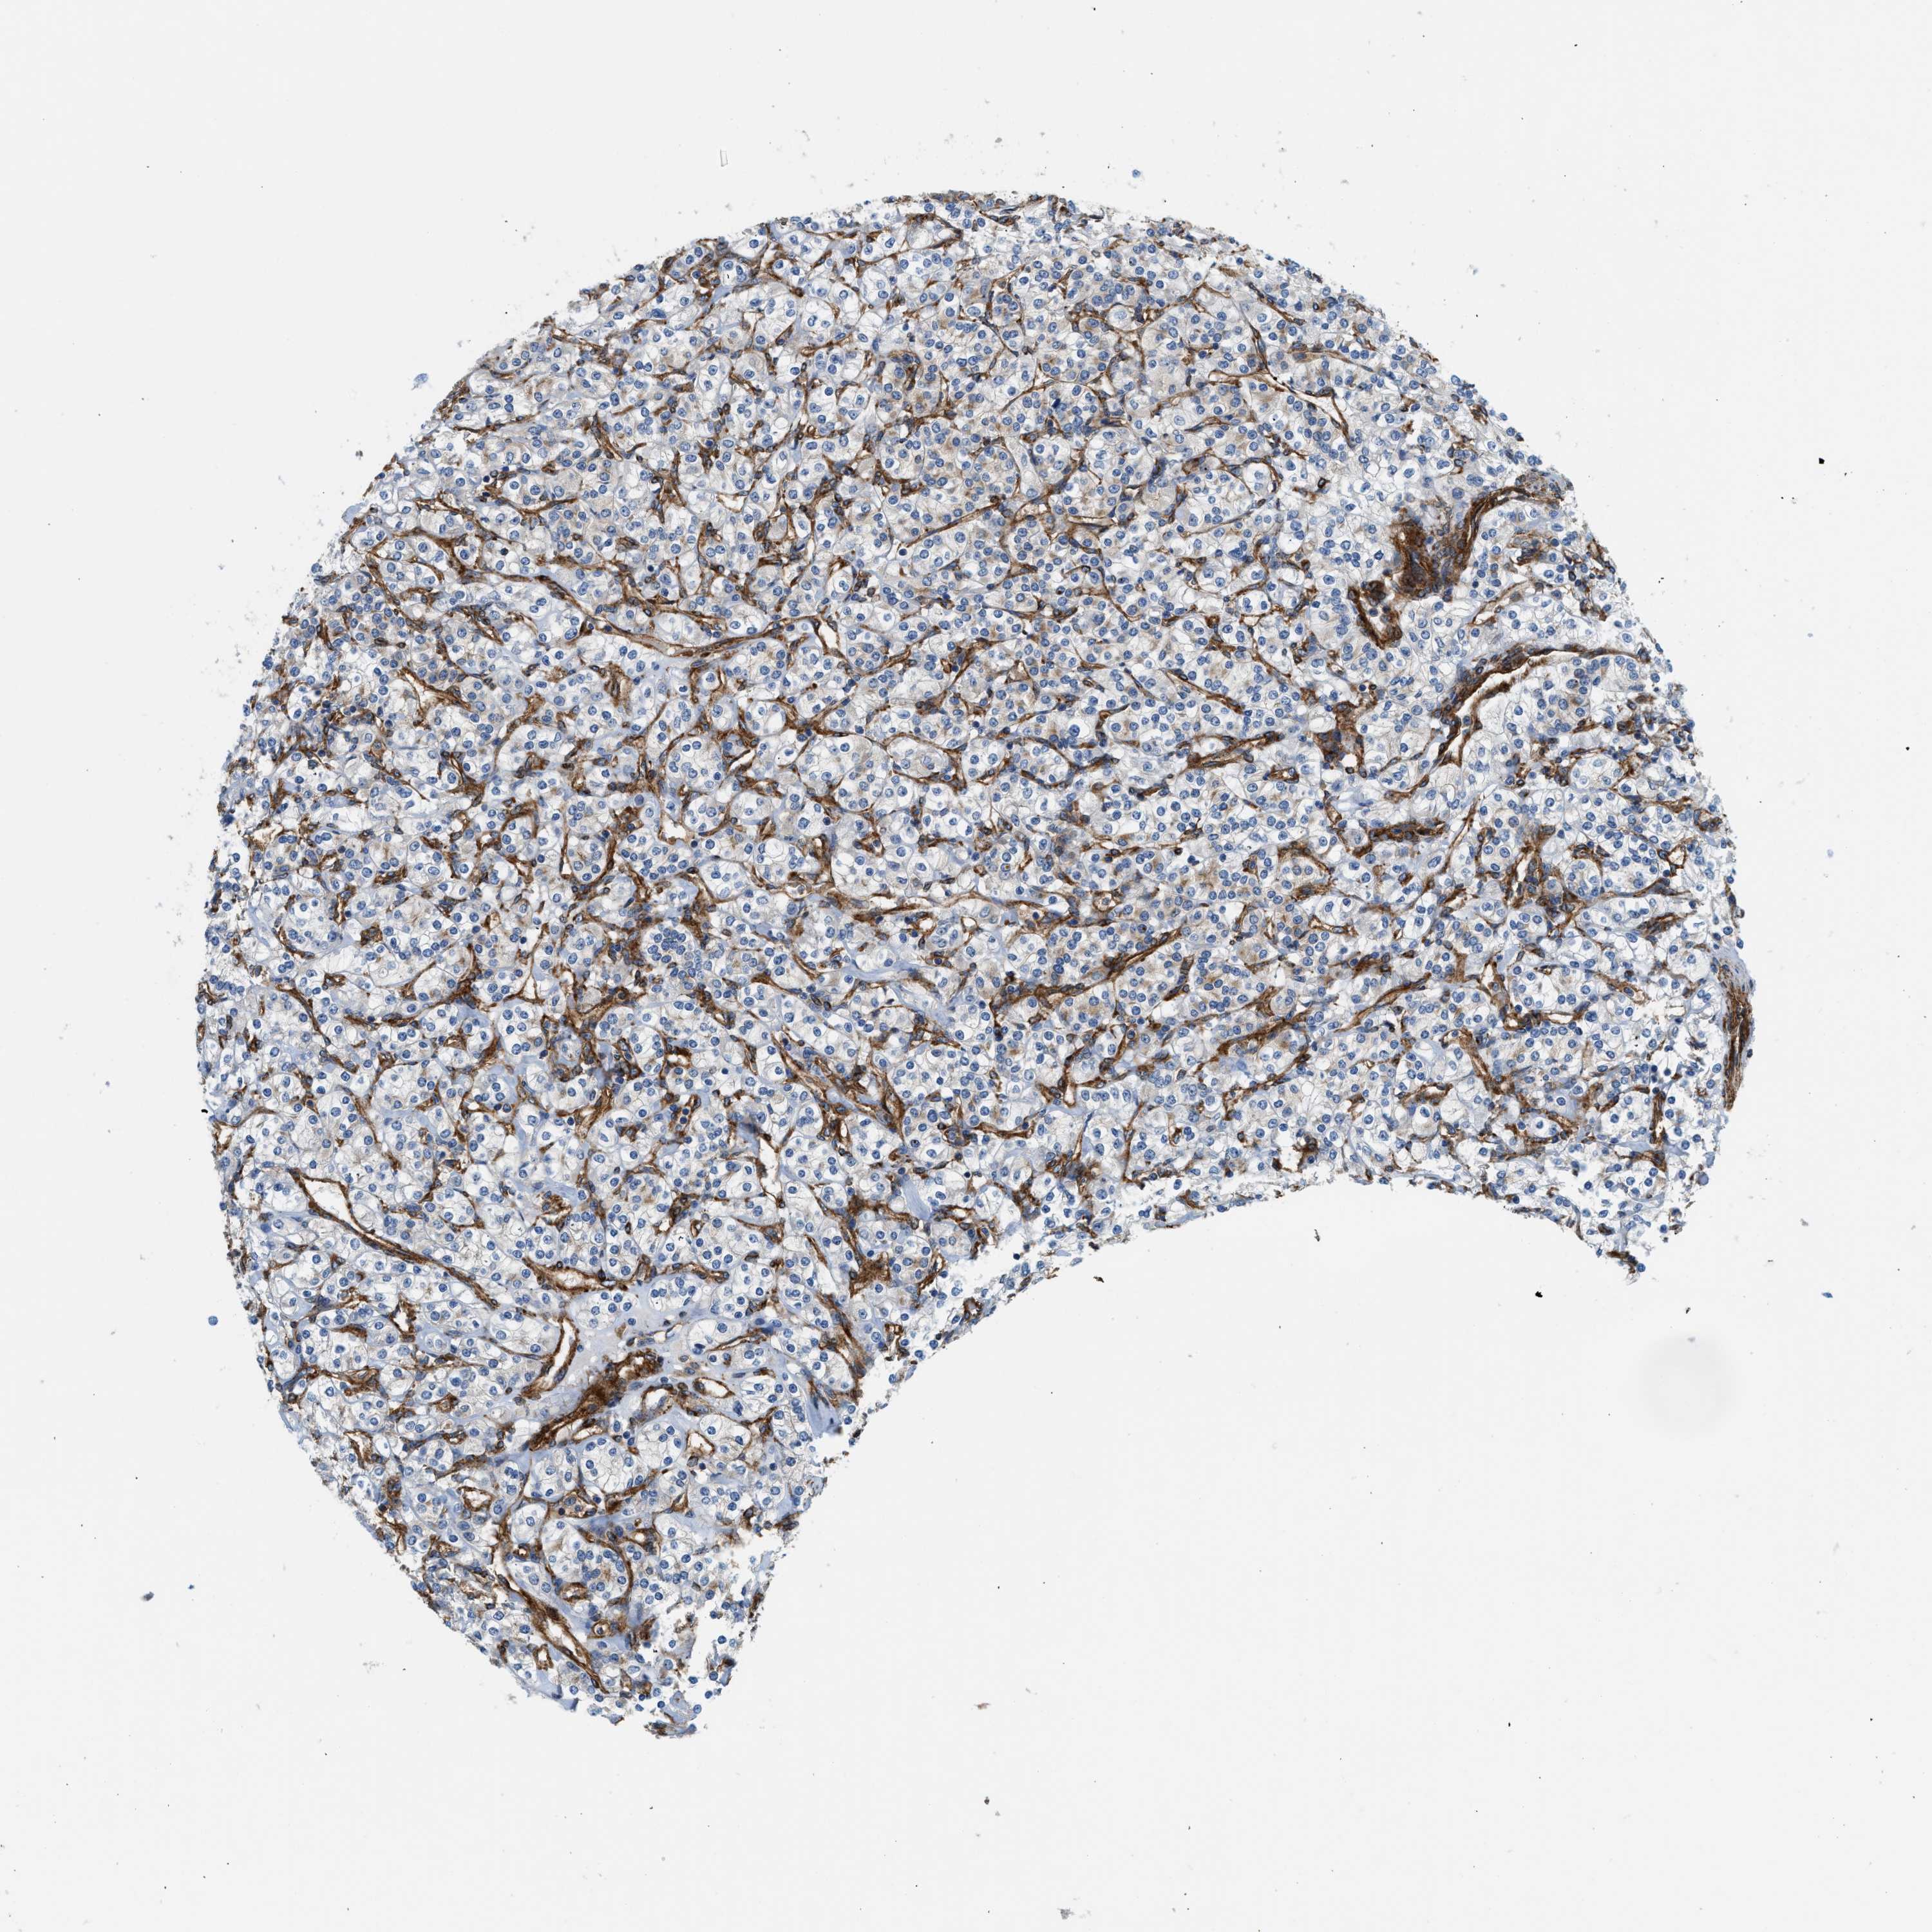

KIDNEY RENAL PAPILLARY CELL CARCINOMA (TCGA) - Interactive survival scatter ploti

The Survival Scatter plot shows the clinical status (i.e. dead or alive) for all individuals in the patient cohort, based on the same data that underlies the corresponding Kaplan-Meier plots. Patients that are alive at last time for follow-up are shown in blue and patients who have died during the study are shown in red.

The x-axis shows the expression levels (FPKM) of the investigated gene in the tumor tissue at the time of diagnosis. The y-axis shows the follow-up time after diagnosis (years). Both axes are complimented with kernel density curves demonstrating the data density over the axes. The top density plot shows the expression levels (FPKM) distribution among dead (red) and alive patients (blue). The right density plot shows the data density of the survived years of dead patients with high and low expression levels respectively, stratified using the cutoff indicated by the vertical dashed line through the Survival Scatter plot. This cutoff is automatically defined based on the FPKM cutoff that minimizes the p-score. The cutoff can be changed by dragging the vertical line or by entering a cutoff value in the square labeled "Current cut-off".

Under the Survival Scatter plot the p-score landscape (black curve; left axis) is shown together with dead median separation (red curve; right axis). Dead median separation is the difference in median mRNA expression between patients who have died with high and low expression, respectively. It is calculated as follows: median FPKM expression of dead patients with high expression - median FPKM expression of dead patients with low expression. This is intended to aid the user in visually exploring custom cutoffs and the associated p-scores and dead median separation.

Individual patient data is displayed and can be filtered by clicking on one or more of the category buttons on the top of the page. Categories describing expression level and patient information include: high, low, alive, dead, female, male and tumor stages. The scale of the x-axis can be toggled between linear and log-scale by clicking on the "x log" button. Mouse-over function shows TCGA ID, patient information and mRNA expression (FPKM) for each patient.

& Survival analysisi

Kaplan-Meier plots summarize results from analysis of correlation between mRNA expression level and patient survival. Patients were divided based on level of expression into one of the two groups "low" (under cut off) or "high" (over cut off). X-axis shows time for survival (years) and y-axis shows the probability of survival, where 1.0 corresponds to 100 percent.

HIP1 is not prognostic in Kidney Renal Papillary Cell Carcinoma (TCGA)